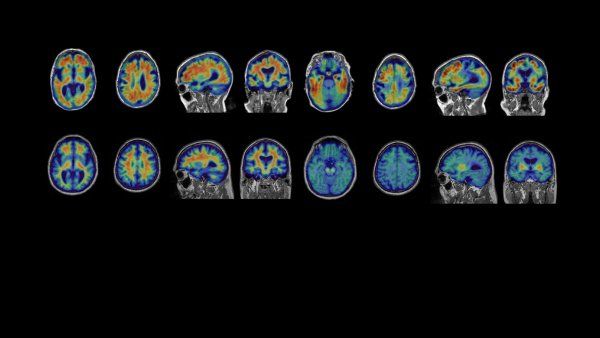

As its name implies, FTD is a fatal disease that destroys cells, or neurons, that comprise the frontal and temporal lobes of the brain — as opposed to Alzheimer’s which mainly affects brain’s memory centers in the hippocampus. Early symptoms of FTD include personality changes, such as increased erratic or compulsive behavior. Patients later experience difficulties speaking and reading, and often suffer from long-term memory loss. FTD is usually diagnosed between the ages of 40 and 65, with death occurring within 2 to 10 years after diagnosis. No drug exists to slow, halt or reverse the progression of FTD.